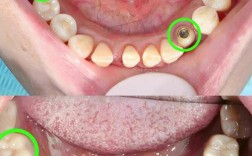

🦷 1. 单颗牙齿缺失

- 情况: 一颗牙齿因蛀牙、外伤、牙周病等原因无法保留而被拔除,或者先天缺失。

- 种植牙优势: 独立修复,不损伤邻牙,稳固,美观,功能接近天然牙。